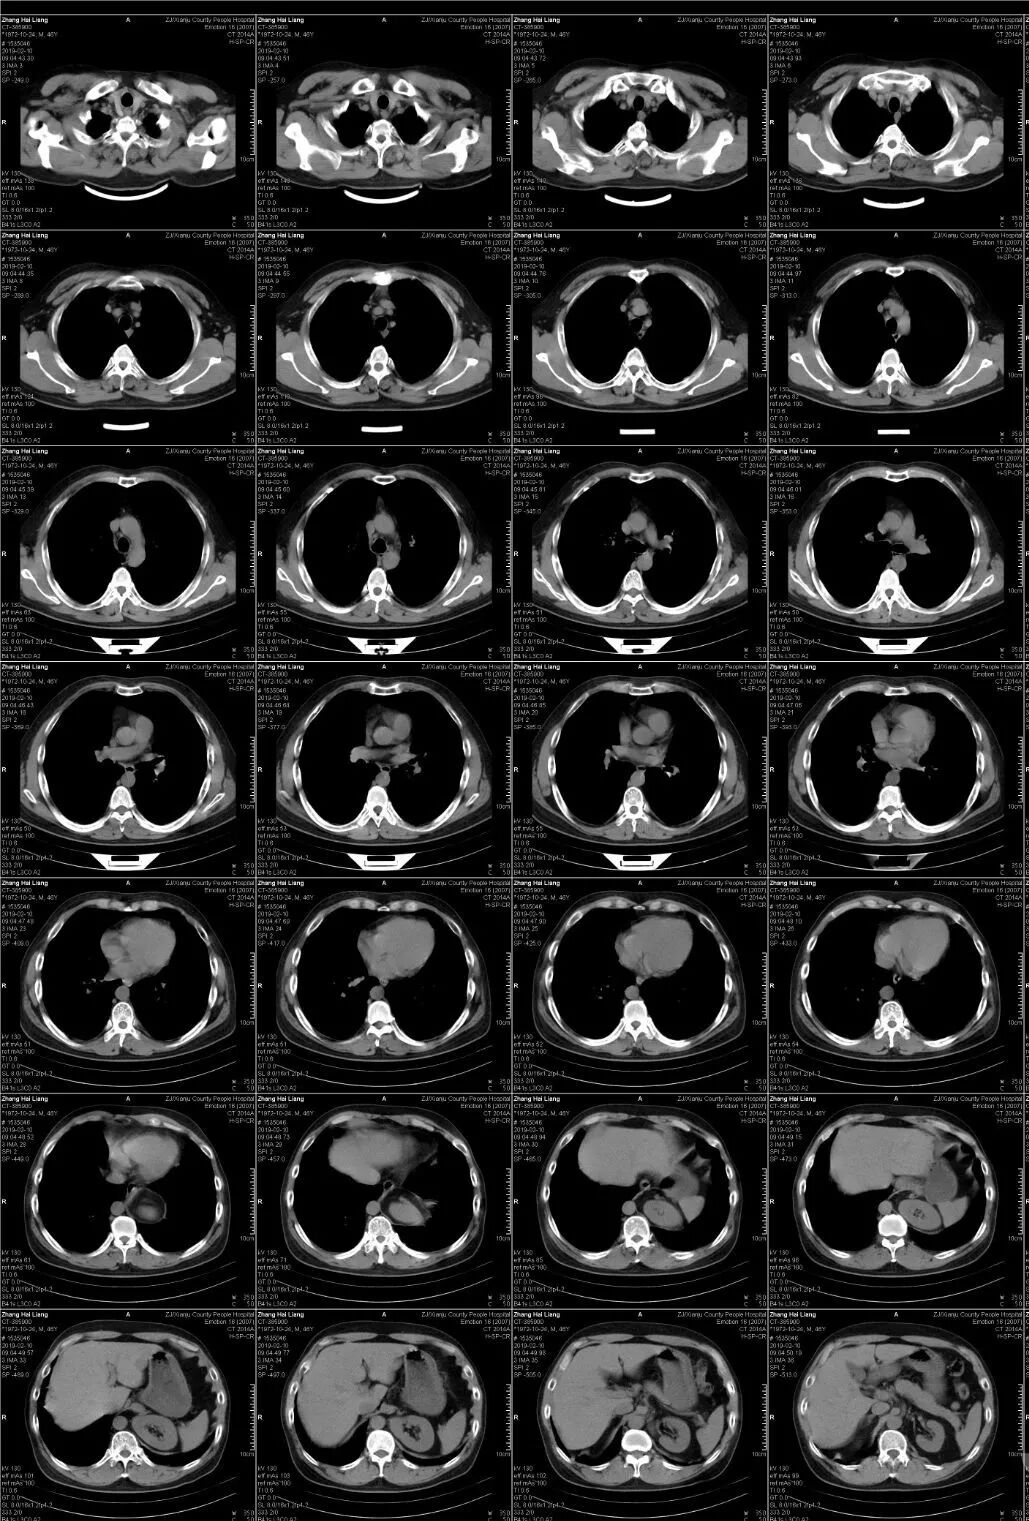

CT即电子计算机断层扫描,它是利用精确准直的X线束、γ射线、超声波等,与灵敏度极高的探测器一同围绕人体的某一部位作一个接一个的断面扫描,供完整的三维信息,具有扫描时间快,图像清晰等特点,可用于多种疾病的检查。

CT的辐射剂量相较于X光片大一点,普通健康体检检查尽量选择低剂量CT筛查而不是常规CT,怀孕妇女不宜进行CT检查。

在平扫CT的基础上,静脉注射造影剂(常用碘对比剂),通过血液循环跑到全身组织器官中,相当于给平扫的CT润色一番,有助于更加准确地分辨血液循环丰富的器官组织病变,如肿瘤。

一般来说,如果普通平扫CT能看清楚病变,并能做出明确的影像学诊断,那就不需要进一步做增强CT了,否则,需要完善增强CT以明确诊断。

极少部分人会对造影剂有不良反应,故检查时需要医护人员及家属或朋友陪同。

CT检查的作用

头部 脑出血、脑梗塞、动脉瘤、血管畸形、各种肿瘤、外伤、出血、骨折、先天畸形等可清楚显示脑挫裂伤、急性脑内血肿、硬膜外及硬膜下血肿、颅面骨骨折、颅内金属异物等,而且比其它任何方法都要敏感。CT诊断急性脑血管疾病如高血压脑出血、蛛网膜下腔出血、脑动脉瘤及动静脉畸形破裂出血、脑梗塞等有很高价值,急性出血可考虑作为首选检查。

胸部 肺、胸膜及纵膈各种肿瘤、肺结核、肺炎、支气管扩张、肺脓肿、囊肿、肺不张、气胸、骨折等;对于显示肺部病变有非常满意的效果,对肺部创伤、感染性病变、肿瘤等均匀有很高的诊断价值。对于纵隔内的肿物、淋巴结以及胸膜病变等的显示非常清晰也令人满意,可以显示肺内团块与纵隔关系等。

腹、盆腔:各种实质器官的肿瘤,外伤,出血、肝硬化、胆结石、泌尿结石、积水、膀胱、前列腺病变、某些炎症、畸形等能清晰的显示解剖的准确部位病变程度,对病变分期等有较高价值,有助于临床制定治疗方案,尤其对于手术科室的手术定位有重要意义。

脊柱、四肢:骨折。外伤。骨质增生、椎间盘病变、椎管狭窄、肿瘤、结核等;观察肿瘤向软组织浸润的情况,骨折、外伤、椎间盘病变等可以显示细小关节面的病变。

肝脏病变;CT检查对于肝内点位性病变、原发性肝癌或转移性肝癌的形态、轮廓、坏死、出血及生长方式等都可以显示,还可以了解胆、胰、肾等脏器的情况,所以慢性肝炎、肝硬化并存在可疑病变或肝癌的患者,非常有做CT检查的必要。肝CT检查对于早期肝硬化的诊断灵敏度较高。

心血管系统: 可用于心包肿瘤、心包积液等的诊断,急性主动脉夹层动脉瘤CT有肯定的诊断意义,特别是增强扫描具有特征性表现,并可做定性诊断。